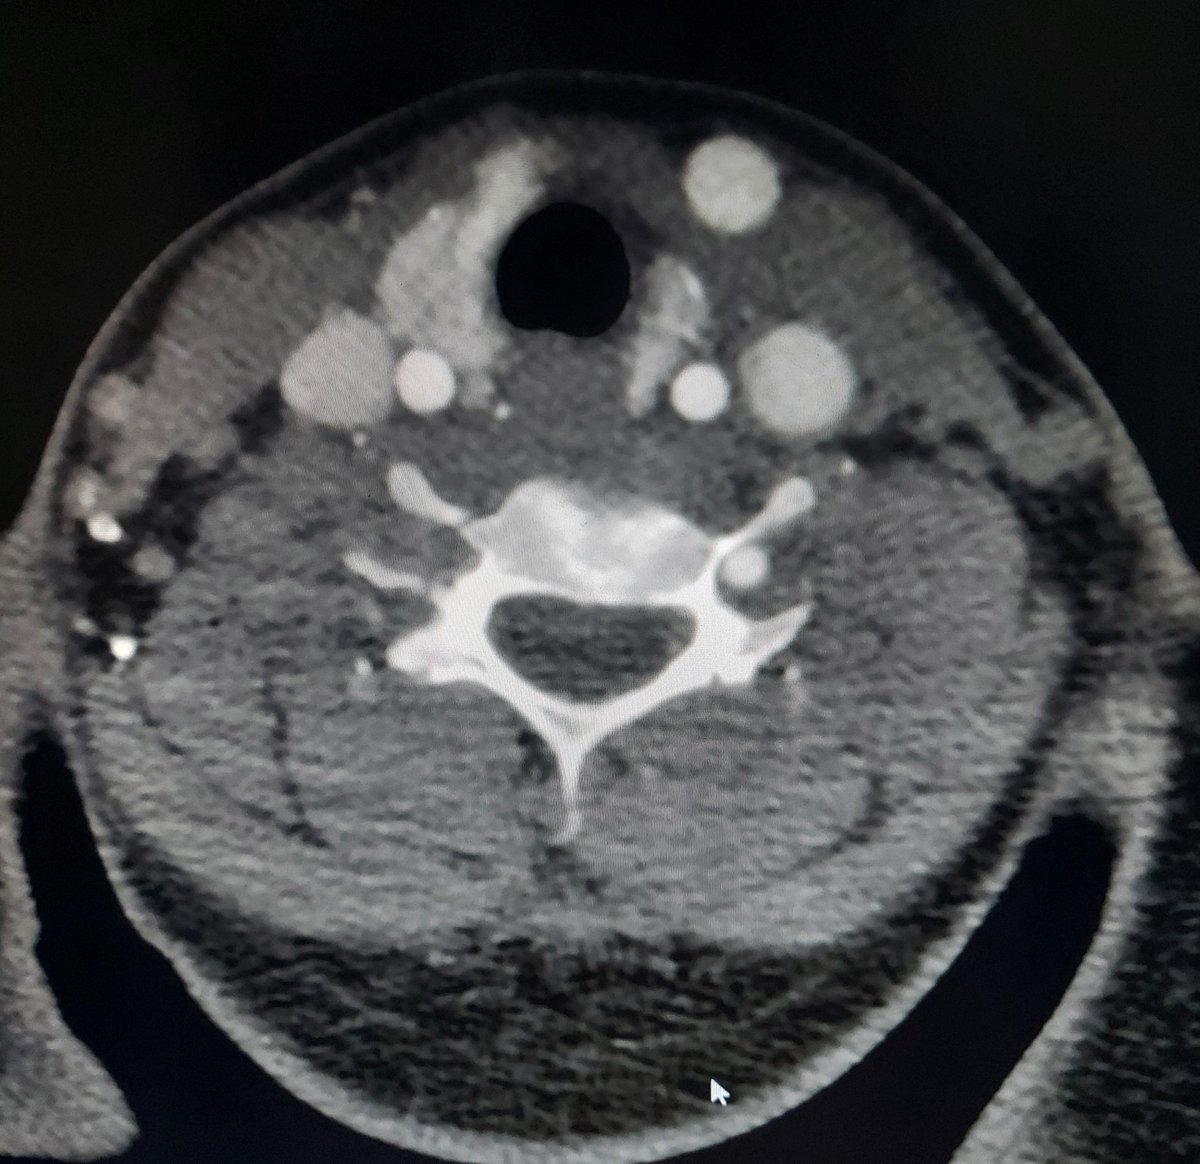

1/2 Hey #neurorad #radres A wise radiologist said, It's always difficult to find when something is missing! 30yr male with trauma MR C.spine done,based on which CT angio done later ✅️Always look for the flow voids in any MR sequence/scan ✅️Always compare with opposite side🧐

Hey #neurorad #radres A wise radiologist said, It's always difficult to find when something is missing!

30yr male with trauma

MR C.spine done,based on which CT angio done later

✅️Always look for the flow voids in any MR sequence/scan

✅️Always compare with opposite side🧐